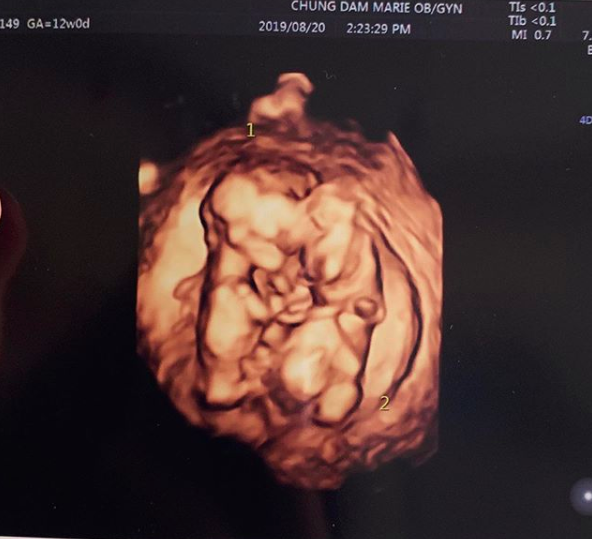

율희는 28일 밤 개인 SNS에 쌍둥이 초음파 사진과 함께 둘째 임신 소감글을 게재했다.

율희는 "짱이(첫째 재율)의 쌍둥이 동생들 소식 듣고 많은 분들께서 축하해주셔서 너무 감사하다"며 "요즘 입덧이 너무너무 심해서 정신을 못 차리고 있는데 그만큼 누구보다 고생해주는 남편과 어머님 덕분에 별 탈 없이 행복하게 태교 중"이라고 강조했다. 특히 율희는 "쌍둥이들은 이렇게 서로 꼭 붙어 잘 크고 있다"며 "다시 한번 축하해주셔서 감사드린다"고 덧붙였다.

![[사진=율희 SNS] 율희가 직접 공개한 쌍둥이 초음파 사진.](https://file.osen.co.kr/article/2019/08/28/201908282239779541_5d668a1dac18b.png)

둥이들은 이렇게 서로 꼭 붙어 잘 크고 있답니다. 다시 한번 축하해주셔서 감사드려요.